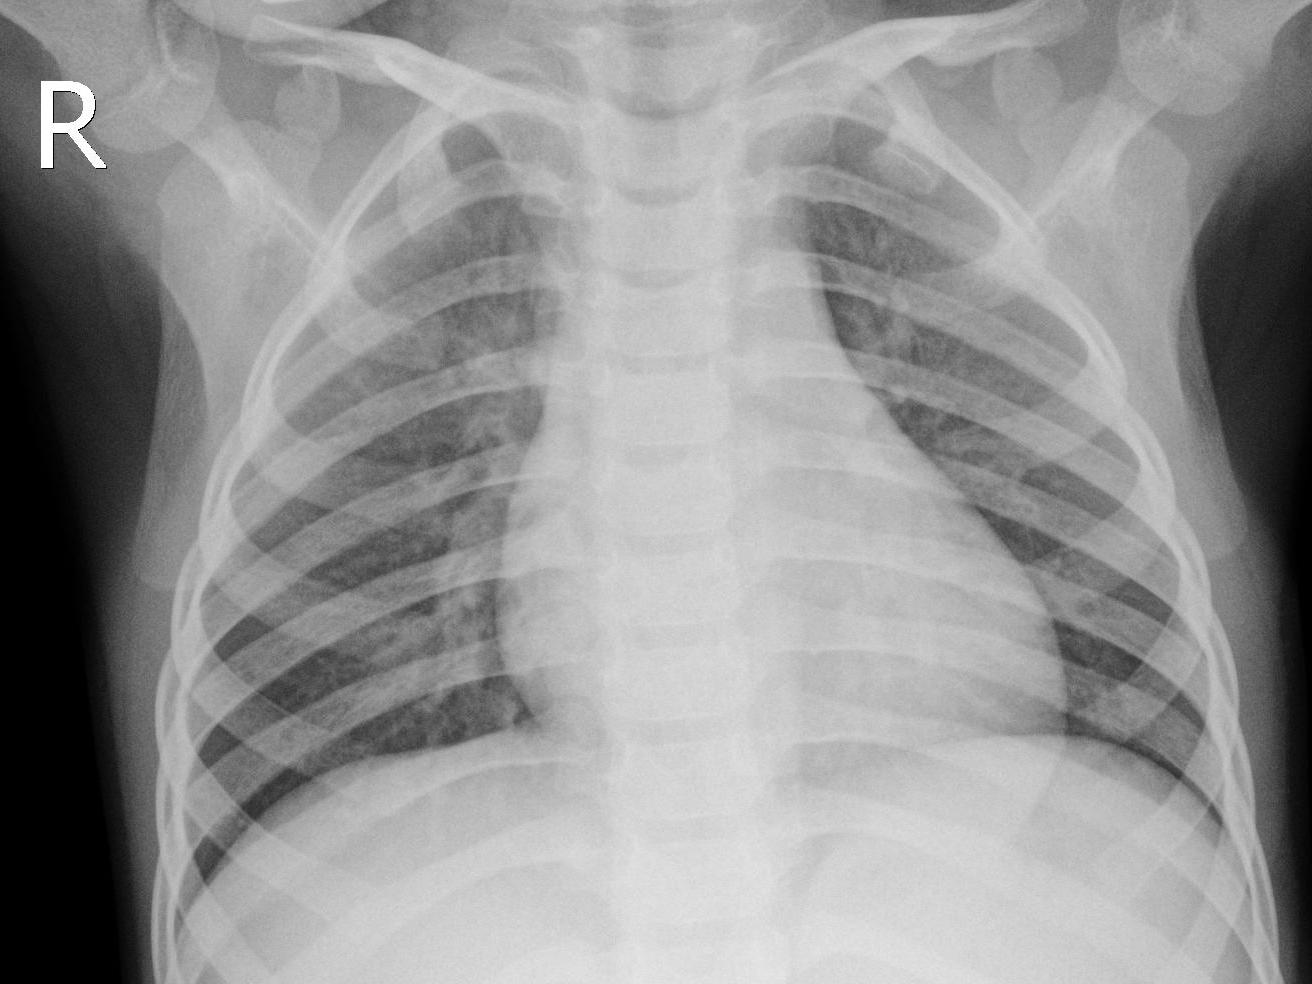

This dataset comprises 5,856 CXR images, divided into three categories: Normal, Bacterial Pneumonia, and Viral Pneumonia. For the purpose of this study, we frame the problem as a two-class classification task distinguishing between a healthy person (Normal) and one having any type of pneumonia (Pneumonia). This choice aligns with previous studies in this field [singh2023pneumonia, ayan2022diagnosis, szepesi2022detection]. The sample images from each class are shown in Figure 2.